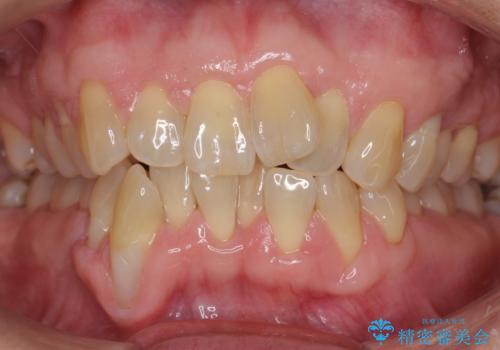

前歯のがたつき インビザラインで抜歯矯正

- 前歯のがたつきを主訴に来院。

右下の犬歯が歯ぐきが痩せて、歯肉退縮しておりそれを抜歯しました。

上の前歯はIPRを行なっています。

右下の犬歯の1本抜歯で最小限の抜歯で並べることができました。